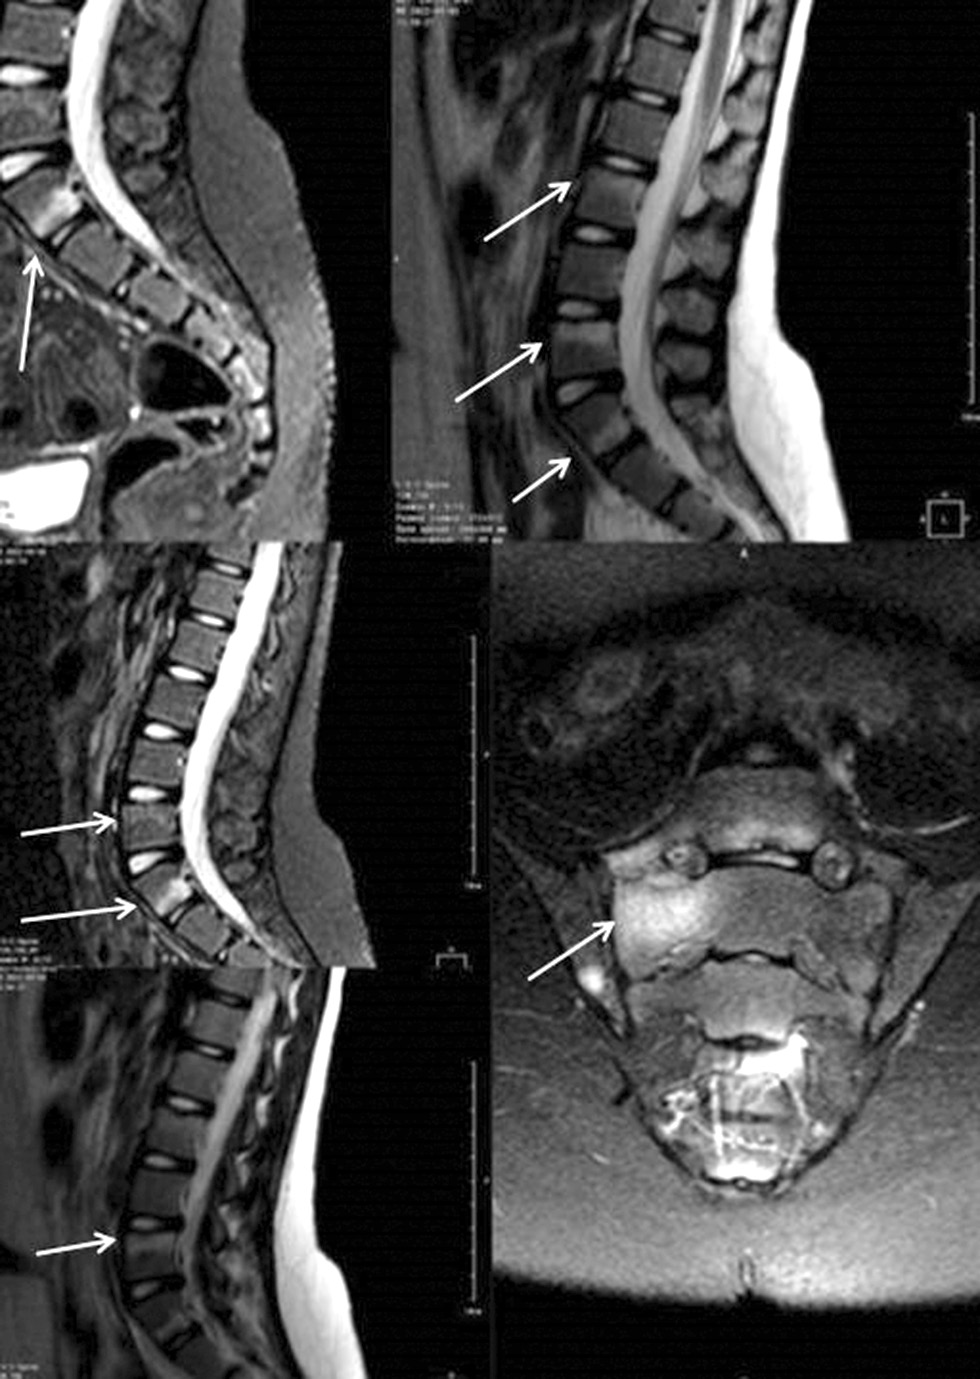

MRI is the method of choice for evaluating axial lesions. In ERA, MRI is most often used to diagnose sacroiliitis (Fig. 5), spondylitis, and arthritis of the peripheral joints and assess bone marrow edema. The earliest sign of sacroiliitis is bone marrow edema in the subchondral region of the synovial part of the sacroiliac joints. Additional signs are synovitis, capsulitis, and enthesitis. In pediatric patients, difficulties in diagnosing sacroiliitis are associated with the structural characteristics of the skeleton. A hyperintense signal may be registered from the apophyseal cartilage, which is not considered bone marrow edema. Edema is defined as a sign of inflammation if the signal is hyperintense compared with the signal from visible metaphyseal equivalents (iliac crest apophysis) on STIR [23]. Erosion indicates a long-term inflammatory process. According to the Assessment of Spondyloarthritis International Society (ASAS) consensus, significant sacroiliitis in adults is determined when a site of bone marrow edema in one anatomical zone is detected on at least two consecutive sections or a zone of bone marrow edema of two or more anatomical zones on at least one section [24]. According to modern concepts, any radiation findings of the sacroiliac joint site should be compared with the clinical presentation to avoid under- or overdiagnosis.

Fig. 5. Vertebral spondylodiscitis and sacroiliitis in a 9-year-old girl with enthesitis-related arthritis (magnetic resonance imaging, changes are indicated with arrows)

A 2017 study assessed the validity of the ASAS criteria in pediatric patients with suspected sacroiliitis. Sacroiliitis was diagnosed by MRI in 30 of 109 patients, whereas only 14 met the ASAS criteria. The low sensitivity of the criteria is explained by the need for the presence of bone marrow edema in at least two sections. The most common signs of sacroiliitis in pediatric patients were bone marrow edema in one section, synovitis, and capsulitis [25].